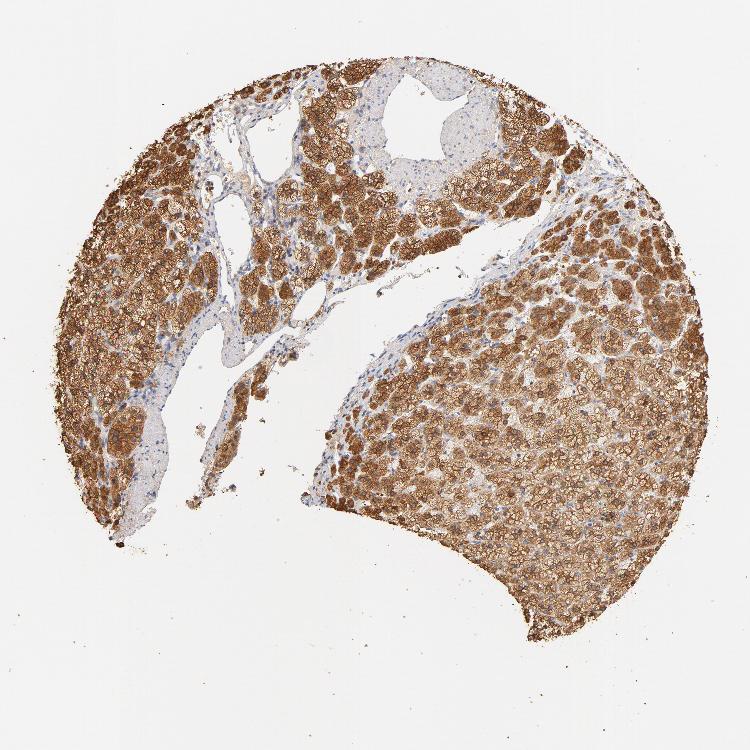

ADRENAL GLAND - Antibody stainingi

Antibody staining in the annotated cell types in the current human tissue is reported as not detected, low, medium, or high, based on conventional immunohistochemistry profiling in selected tissues. This score is based on the combination of the staining intensity and fraction of stained cells.

Each image is clickable and will lead to virtual microscopy that enables deeper exploration of all samples and also displays staining intensity scores, fraction scores and subcellular localization as well as patient and tissue information for each sample.

Antibody HPA021616Antibody CAB004035Antibody CAB047324Antibody CAB075739

Glandular cells HighMediumHighHigh